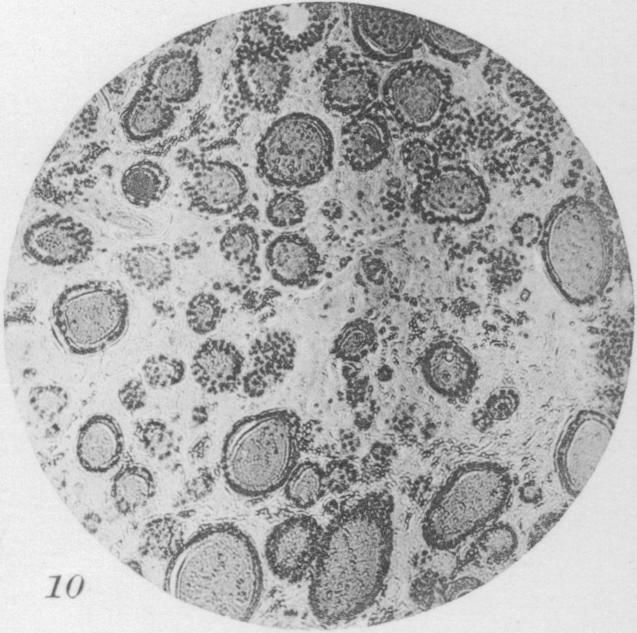

Benign Epithelial tumors of the Thyroid Gland.

J Med Res. 1913 Jan;27(3):229-268.5.